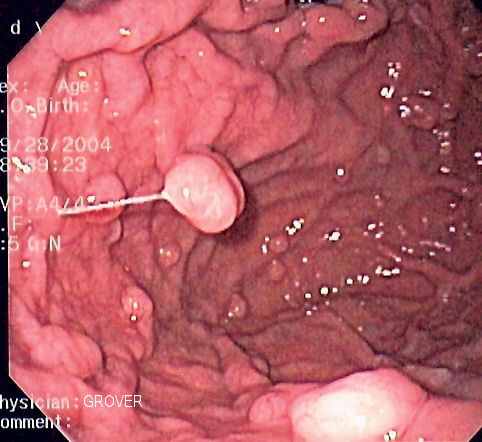

위선 폴립(polyp (medicine))의 내시경 사진